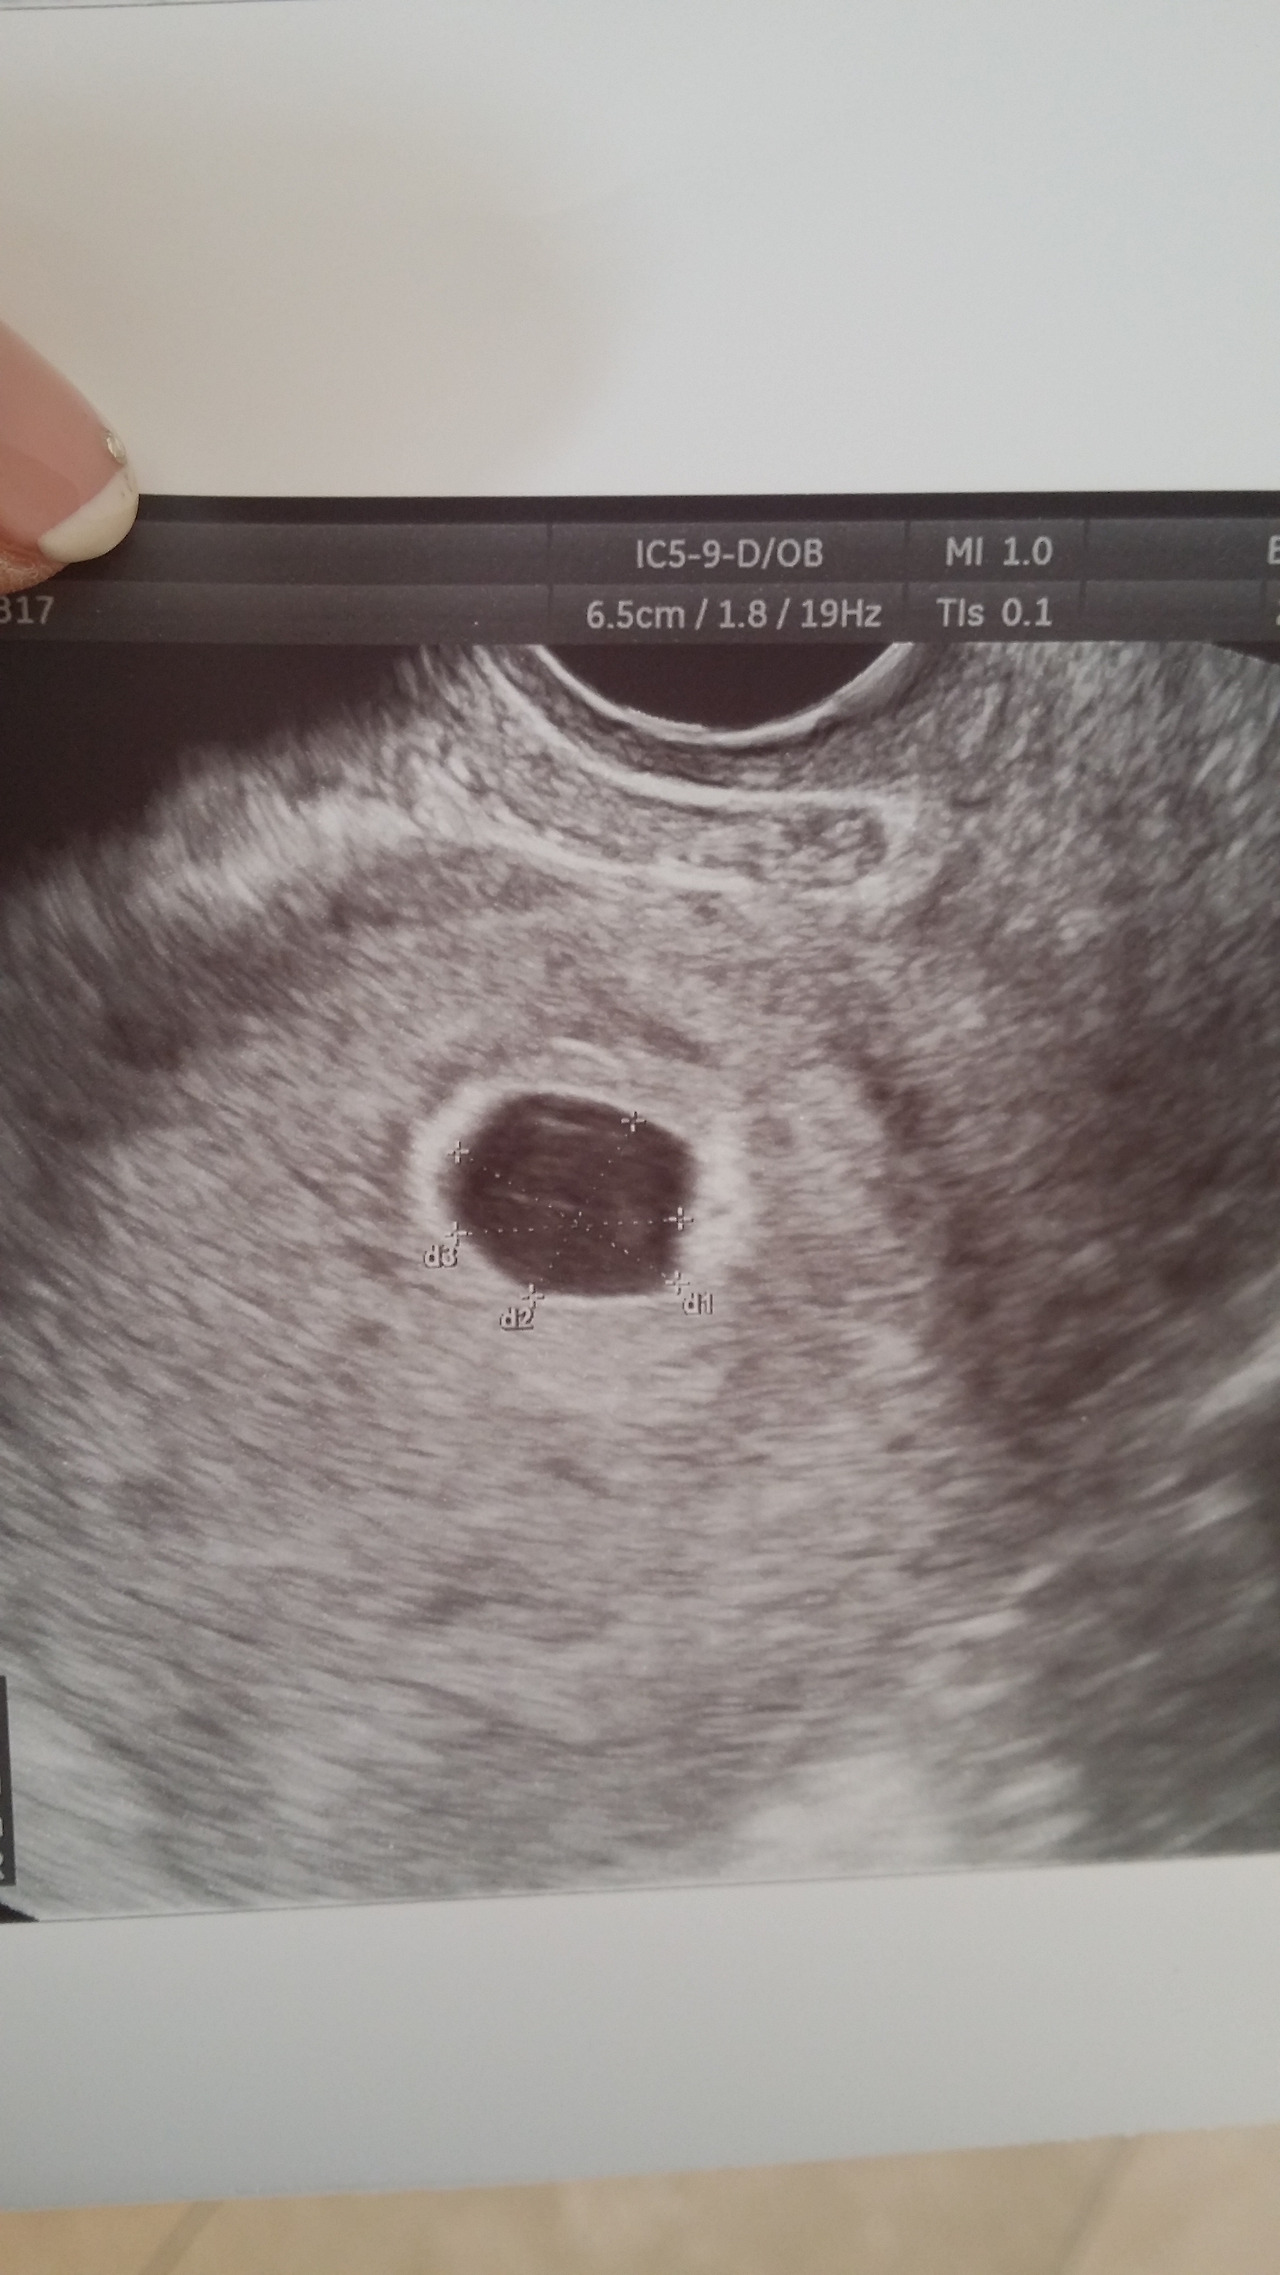

약 10일 후 초음파를 통해 남의 자궁에 자신의 존재를 드러낸 작은 인간을 만났다.

20141216_140903.jpg 이 작은 점은 이미 인간인 것이다.